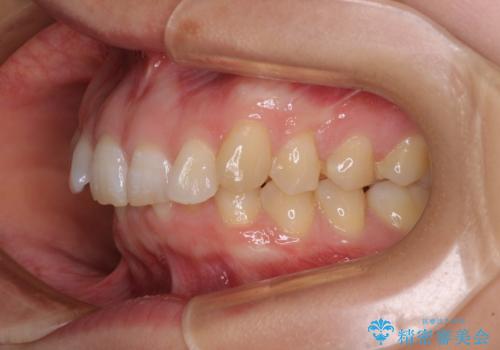

カリエールディスタライザーや部分的なワイヤー矯正を併用したことで、確実かつ短期間で治療を終えることができました。